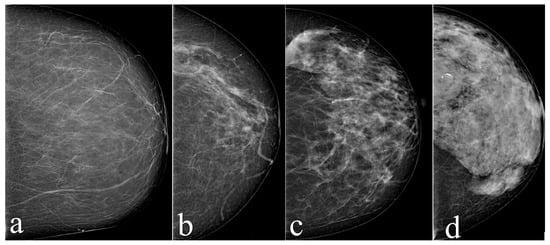

PSO-Based Ensemble Learning Enhanced with Explainable Artificial Intelligence for Breast Glandular Dose Estimation in Mammography

Objectives: This study aims to predict patient-specific Average Glandular Dose (AGD) in mammography using machine learning-based models to support personalised radiation dose optimisation and reduce unnecessary exposure during breast cancer screening. Methods: A retrospective dataset of 671 female patients who underwent full-field digital [...] Read more.

Objectives: This study aims to predict patient-specific Average Glandular Dose (AGD) in mammography using machine learning-based models to support personalised radiation dose optimisation and reduce unnecessary exposure during breast cancer screening. Methods: A retrospective dataset of 671 female patients who underwent full-field digital mammography between 2020 and 2024 was analysed. Right craniocaudal (CC) images were used to construct a structured dataset including mAs, kVp, compressed breast thickness, air kerma (k_air), half-value layer (HVL), and breast pattern. Five regression-based machine learning models (CatBoost, Gradient Boosting, Random Forest, Extra Trees, and AdaBoost) and their Particle Swarm Optimisation (PSO)-enhanced versions were evaluated. Model performance was assessed using MSE, RMSE, MAE, MAPE, and R2. SHAP analysis was applied to interpret model predictions and determine variable importance. Results: PSO integration significantly reduced prediction errors, particularly in boosting-based models. The CatBoost + PSO model achieved the best performance (RMSE = 0.0100, MAPE ≈ 1.74%, R2 = 0.9846), followed by the Gradient Boosting + PSO model (R2 = 0.9787). PSO reduced RMSE and MAPE by approximately 55% and 52%, respectively. SHAP analysis identified k_air, breast thickness, and breast pattern as the most influential factors affecting AGD. Conclusions: Machine learning models enhanced with PSO, especially CatBoost + PSO, provide accurate and reliable patient-specific AGD predictions. The proposed approach enables rapid and clinically applicable dose estimation and highlights breast pattern as a critical parameter influencing glandular dose, supporting personalised radiation dose optimisation in mammography. Full article

Show Figures

Figure 1